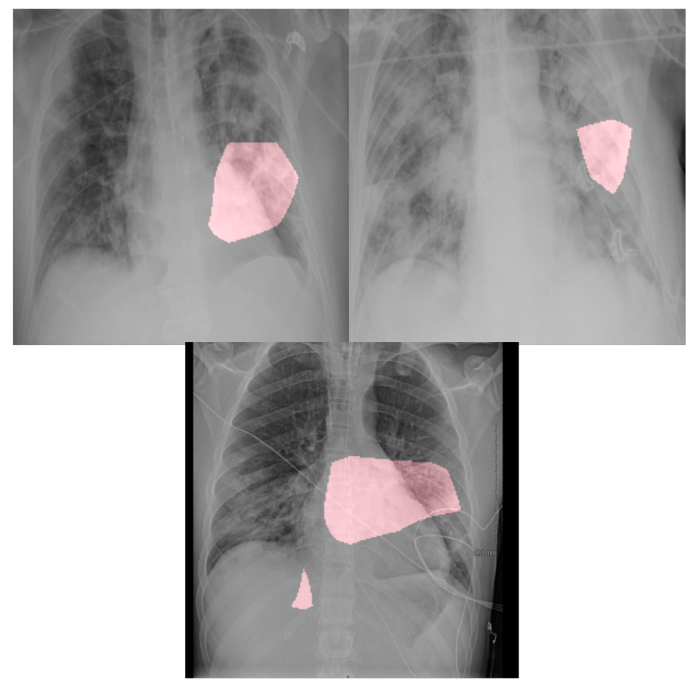

En dehors de la les applications commerciales et industrielles, les CNN ont trouvé leur place dans de nombreux domaines scientifiques. L’une des applications les plus connues des réseaux neuronaux convolutifs est l’analyse de l’imagerie médicale. Il existe déjà de nombreux algorithmes d’apprentissage profond qui examinent les scanners et les rayons X et aident au diagnostic de maladies telles que le cancer. Récemment, les scientifiques ont utilisé les réseaux de neurones convolutionnels pour trouver les symptômes du nouveau coronavirus en radiographie du thorax.

L’attribution de caractéristiques nous aide à mieux comprendre quelles caractéristiques d’un échantillon spécifique ont contribué à la production d’un réseau neuronal. Ces techniques produisent des cartes des points saillants qui mettent en évidence ces caractéristiques. Par exemple, si vous inspectez un classificateur d’images, la carte des points saillants mettra en évidence les parties de l’image sur lesquelles l’IA s’est basée pour déterminer sa catégorie.

Il existe différentes techniques pour produire des cartes des points saillants, notamment GradCAM, LIME et RISE. Ce sont de bonnes méthodes pour inspecter la production des réseaux de neurones afin de comprendre si leurs décisions sont basées sur les bonnes ou les mauvaises caractéristiques.

Exemples de cartes des points saillants produites par RISE